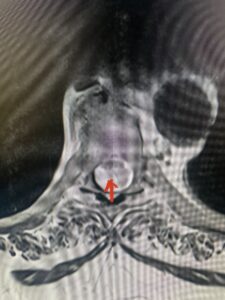

Fig. 1b Axial T2-weighted thoracic MRI demonstrating spinal cord compression from T10-11 arachnoid cyst (red arrow)

This 67-year-old female presents with progressive heaviness and numbness of the legs and difficulty ambulating. Her right leg was worse than her left. She had right greater than left hip flexor weakness. She was hyperreflexia in her lower extremities. An MRI (Fig. 1) demonstrated an intradural arachnoid cyst at T10-11 with severe spinal cord compression. She also appeared to have an arachnoid cyst above from T4-T8 with anterior displacement and compression of the spinal cord. Because of her severe myelopathy and the findings on MRI the patient underwent laminectomy for surgical decompression of cyst. Intraoperatively the focal arachnoid cyst at T10-11 appeared as a small bubble crushing the spinal cord anteriorly with scarring of the arachnoid with no CSF flow above or below.

The cyst was fenestrated and immediately CSF flow was reestablished. We performed a laminectomy at T6-7 for the upper cyst region which was observed to be more consistent with normal anatomy. We fenestrated the arachnoid. It was felt that the upper level was a secondary phenomenon as a result of CSF flow blockage. Post operatively she had an uneventful course with return of normal strength although she had some residual numbness.